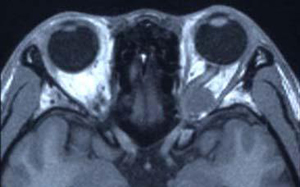

Ⅰ 30歳代女性

左眼窩尖端部腫瘍、病理診断は神経線維腫。

左視力、視野障害を主訴として来院した。摘出手術後視力、視野障害は正常化した。

• 術前MRI